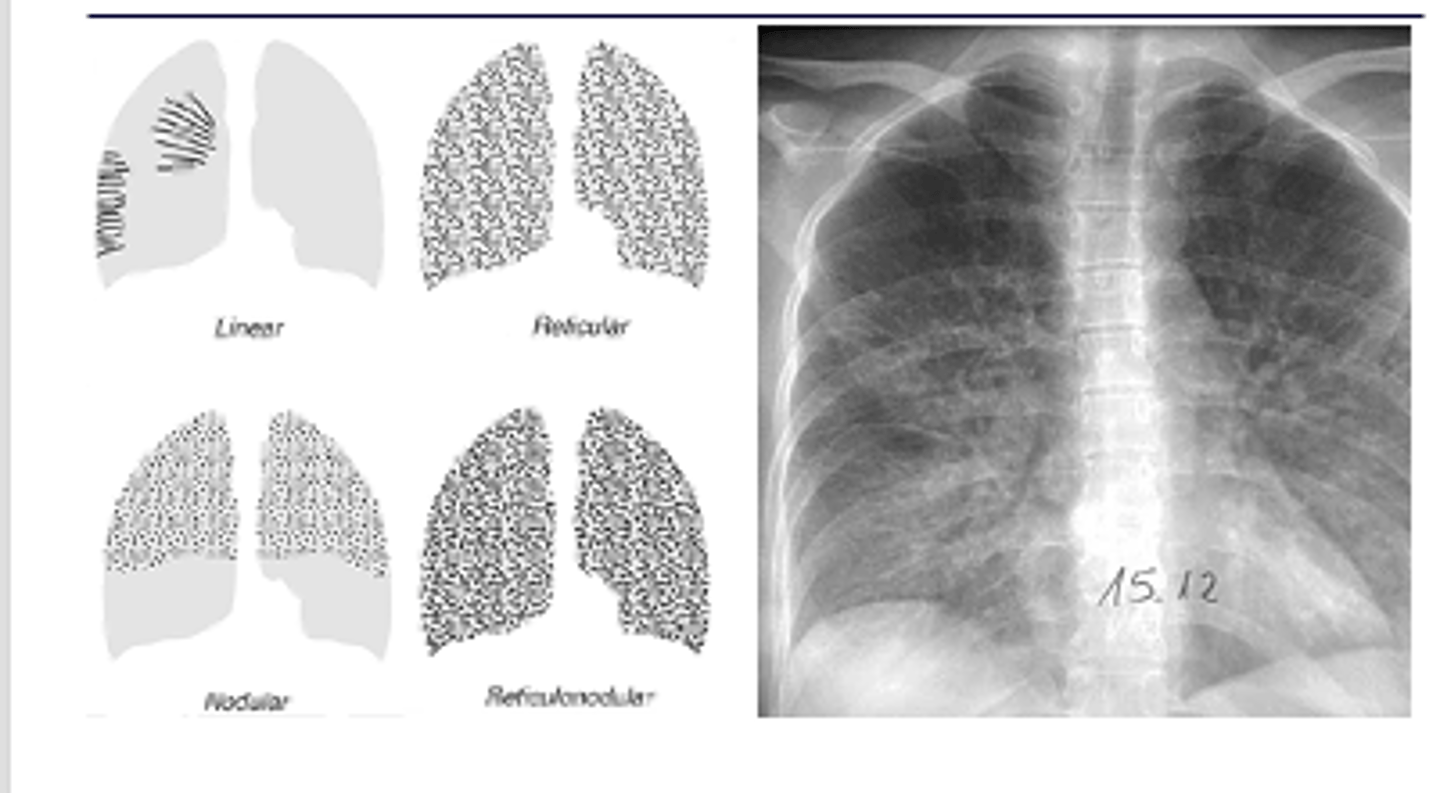

What is reticular opacity? What is this difference between fine and coarse?

Coarse - greatest width of opacity (fine on L and coarse on R)

Describe nodular pattern interstitial infiltrate

Nodular

A nodular pattern consists of multiple round opacities, generally ranging in diameter from 1 mm to 1 cm

<p>Nodular</p><p>A nodular pattern consists of multiple round opacities, generally ranging in diameter from 1 mm to 1 cm</p>